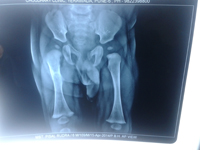

Severe trauma is usually required to injure the lower limb in children. Usual site of fracture is through the diaphysis or metaphysis of bone. Foot injuries are also common in children. These fractures have good remodelling potential hence they can be treated with simple plasters. However femur fractures in older children will usually require nailing or plating. Though the fractures heal quickly, the children sometimes need a longer time to recover and hence will continue to limp even after plaster removal. The children start walking once their pain decreases.